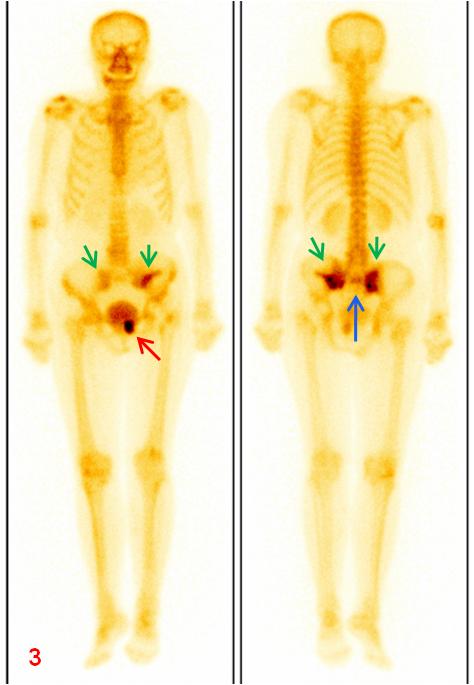

老年女性,1年前因直腸惡性腫瘤于外院行放射治療,此次常規(guī)復(fù)查平掃CT示骶骨及左側(cè)恥骨密度不均勻,左側(cè)恥骨骨質(zhì)斷裂;平掃M(jìn)R示雙側(cè)骶骨翼、左側(cè)髂骨及左側(cè)恥骨異常信號(圖1、2);為進(jìn)一步明確診斷行全身骨顯像ECT檢查(圖3)。

圖3全身骨顯像:雙側(cè)骶髂關(guān)節(jié)(綠箭)、骶骨(藍(lán)箭)及左側(cè)恥骨(紅箭)放射性異常濃聚。

本例患者因惡性腫瘤病史,臨床初步懷疑骨轉(zhuǎn)移,行ECT檢查目的是為了進(jìn)一步明確診斷,評估病變范圍,以指導(dǎo)后續(xù)治療。但ECT影像顯示了典型的“H”形放射性濃聚,結(jié)合患者為絕經(jīng)后女性,存在放射性治療的危險因素,故首先考慮機(jī)能不全骨折,排除了骨轉(zhuǎn)移可能。